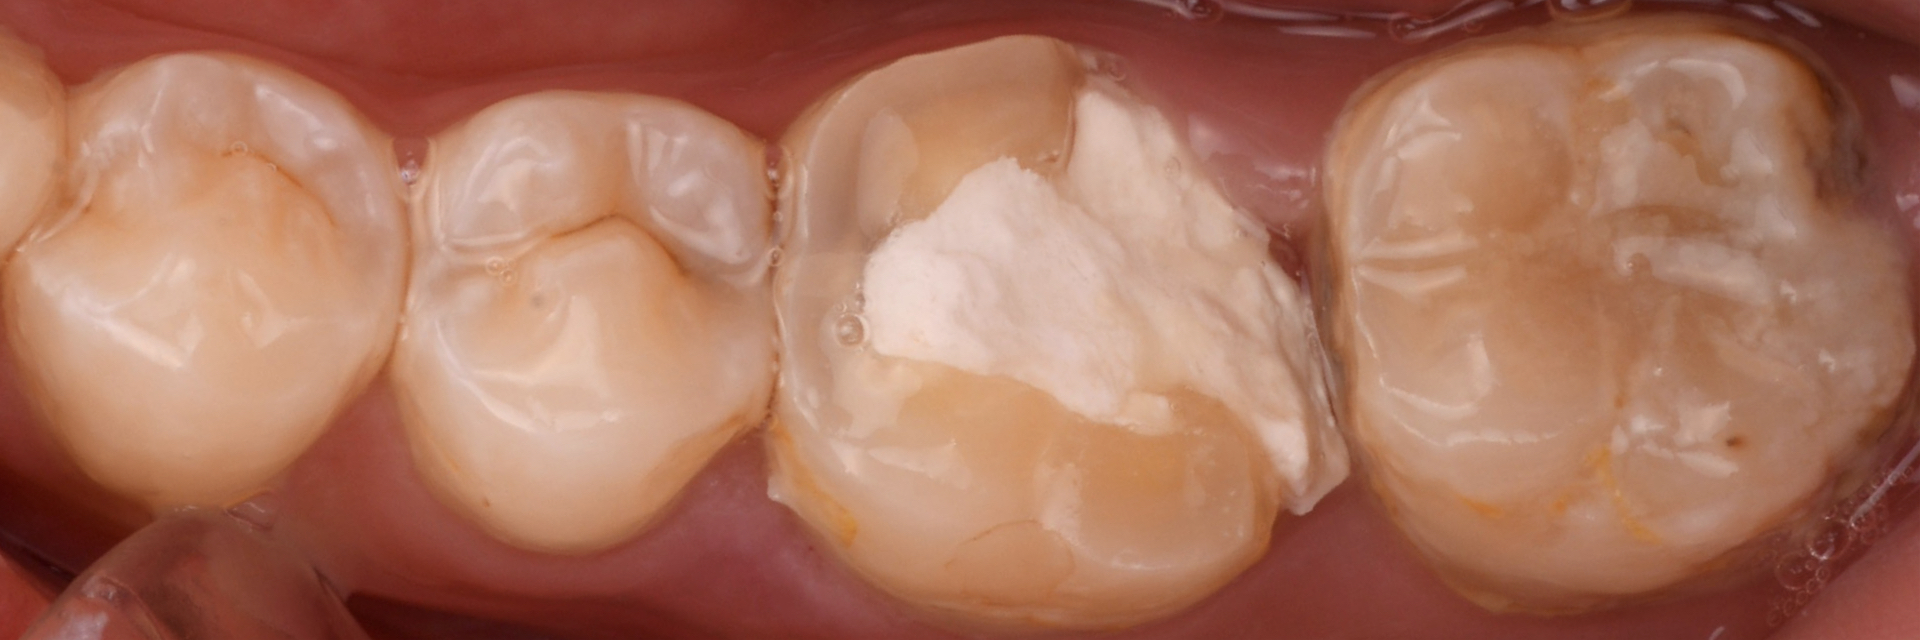

【20代 男性】

奥歯の

大きな虫歯の治療

治療中

ラバーダムを用いてセラミックを装着していきます

主訴 奥歯が痛い

期間 2ヶ月

費用 セラミックアンレー95,000円〜

治療内容 まず炎症が生じている神経の治療を行う

その後に歯冠修復処置をダイレクトレストレーション及びセラミックを用いて行った

治療に伴うリスク 知覚過敏

セラミックの破折